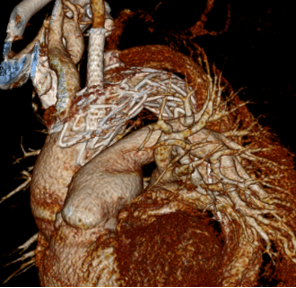

弓部小弯侧动脉瘤,外院TEVAR后IA型内漏

再干预方案:弹簧圈栓塞

弓上分支重建+

近端延伸支架

瘤腔内弹簧圈栓塞